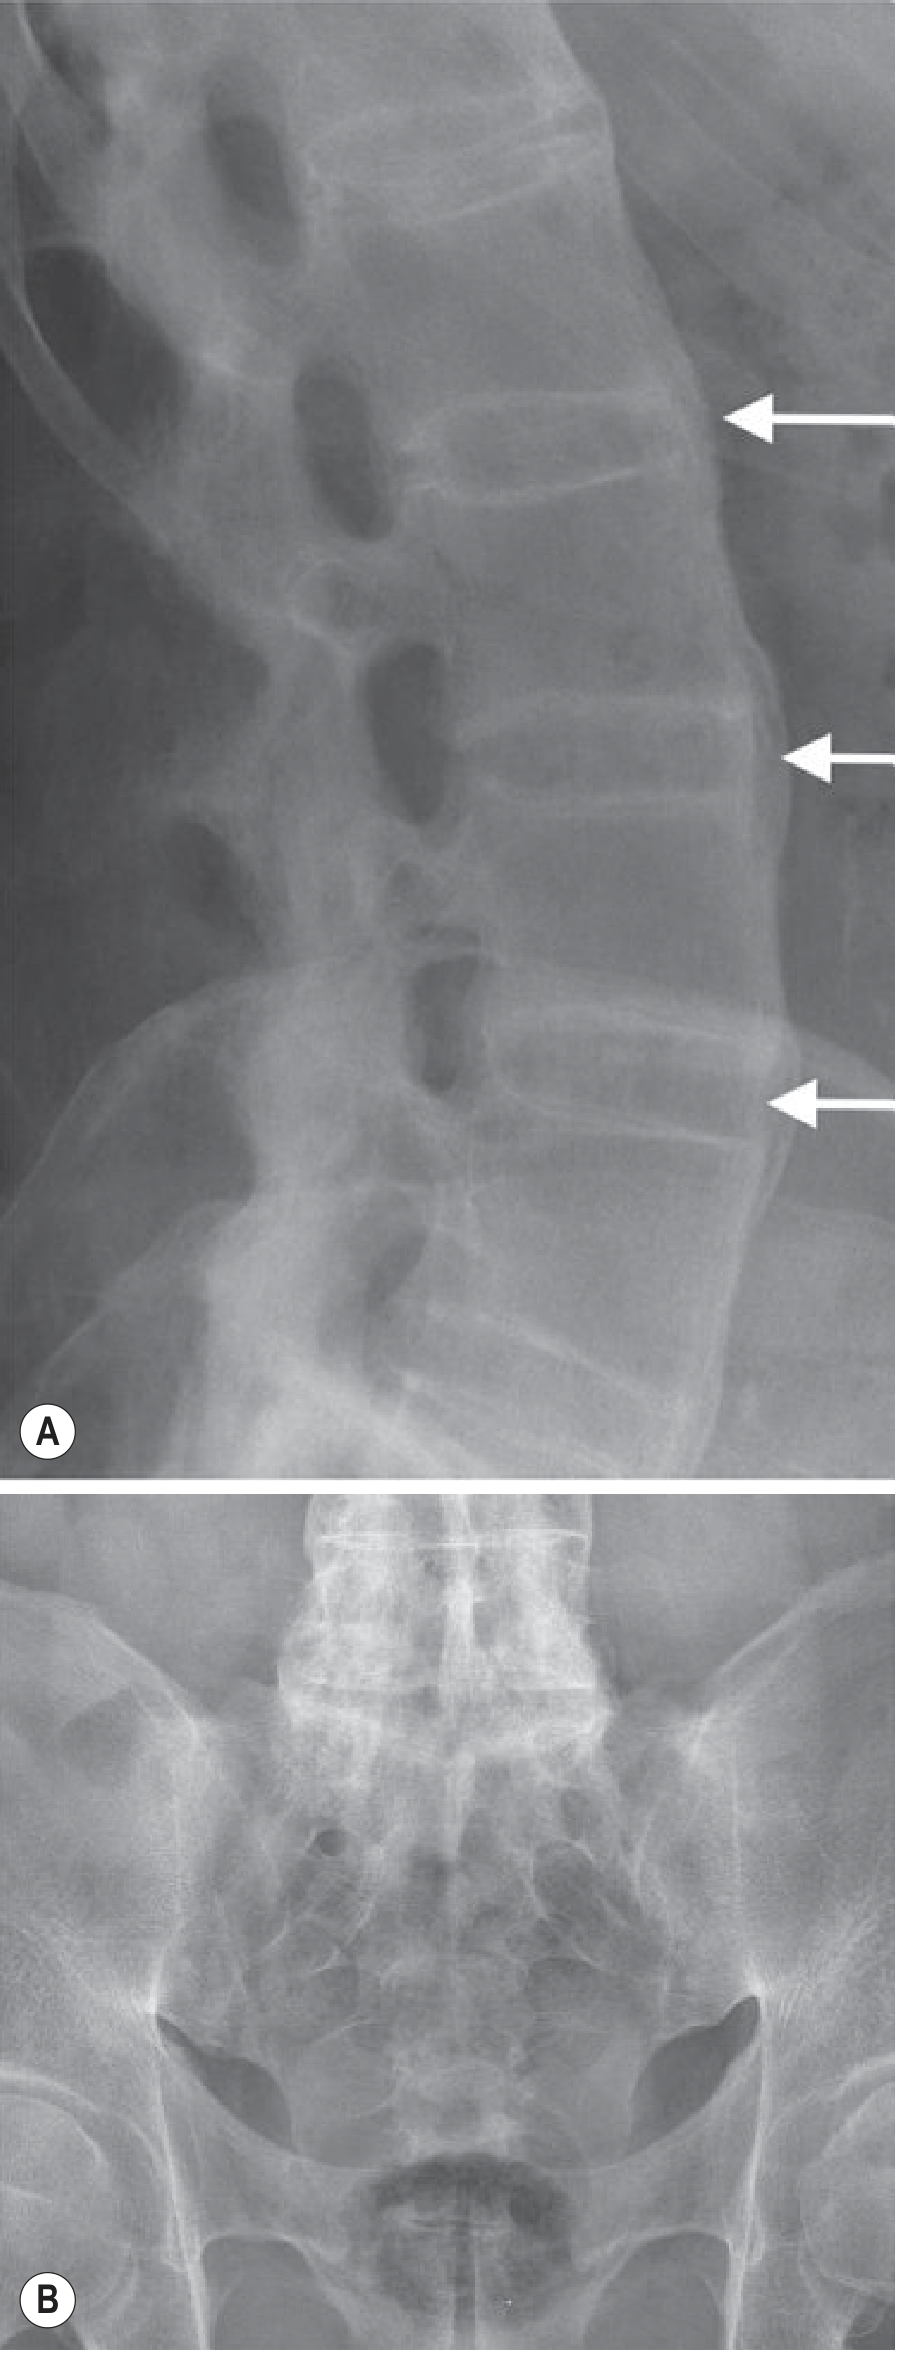

Bamboo Spine X-ray (Advanced AS):

AS with Bamboo Spine — bridging syndesmophytes and fused sacroiliac joints

Fig. Advanced AS: (A) Bridging vertical syndesmophytes seen around intervertebral discs (arrows) with fused facet joints L3–S1. (B) Complete bony fusion of bilateral sacroiliac joints. — Grainger & Allison's Diagnostic Radiology